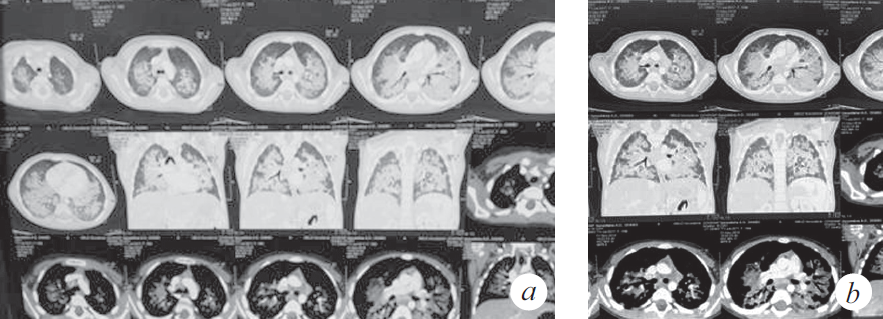

Из анамнеза заболевания известно, что 01.11.2018 ребенок по неосторожности родителей принял внутрь парафиновое масло. Мама стимулировала рвоту, после чего ребенок стал подкашливать. Бригадой скорой медицинской помощи девочка доставлена в стационар по месту жительства с диагнозом: «Острая респираторная вирусная инфекция, ларинготрахеит». О факте случайного приема парафинового масла и стимуляции рвоты мать не сообщила. Первые три дня пациентка находилась в стационаре (детская клиническая больница № 1) и, учитывая улучшение, была выписана под наблюдение участкового врача. На одиннадцатый день заболевания девочка с симптомами внебольничной двусторонней пневмонии была госпитализирована в стационар центральной клинической больницы СО РАН, с дальнейшим переводом в инфекционную больницу. По результатам компьютерной томографии (КТ) органов грудной клетки констатированы признаки диффузного интерстициального заболевания легких (рис. 1). На этом основании заподозрено аспирационное поражение паренхимы легких, вероятность которого подтвердила мать при дополнительном сборе анамнеза.

Рис. 1. Компьютерная томограмма органов грудной клетки (через 3 нед. от дебюта заболевания) (a). Признаки диффузного интерстициального заболевания легких, вероятно, двусторонняя липоидная пневмония, дифференциальный диагноз с альвеолярным протеинозом (b)

Fig. 1. CT scan of the chest (3 weeks after the onset of the disease) (a). Signs of diffuse interstitial lung disease, probably bilateral lipoid pneumonia, differential diagnosis with alveolar proteinosis (b)